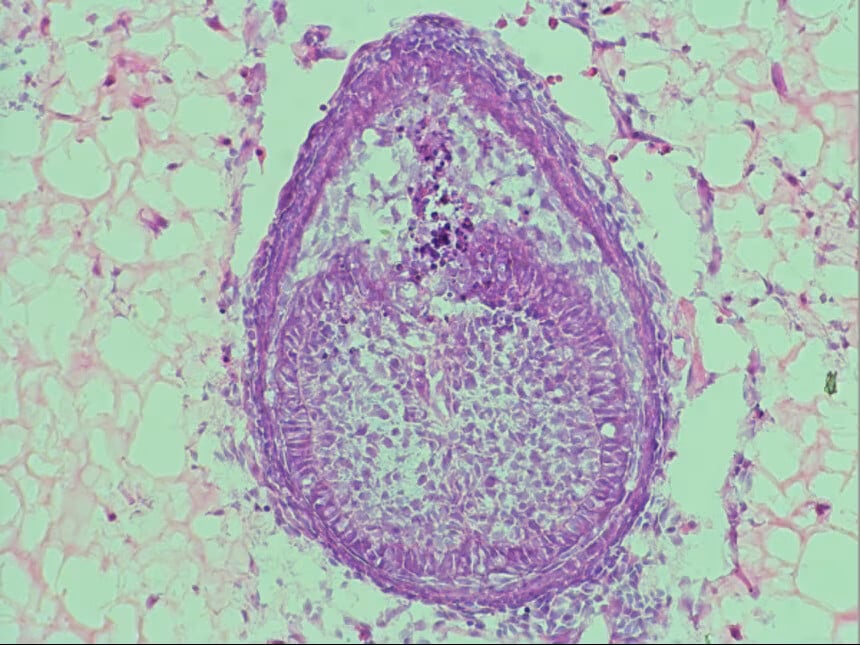

Μέσα σε αυτό το περιβάλλον, τα κύτταρα σχηματίζουν μικροσκοπικές δομές, που μοιάζουν με δόντια, ένα σημαντικό βήμα πριν αντικατασταθούν πλήρως τα εμβρυϊκά κύτταρα ποντικιών με ανθρώπινα. Σε προηγούμενες μελέτες, παρόμοιες δομές είχαν μεταμοσχευθεί σε ποντίκια και εξελίχθηκαν σε δόντια με ρίζες και σμάλτο.